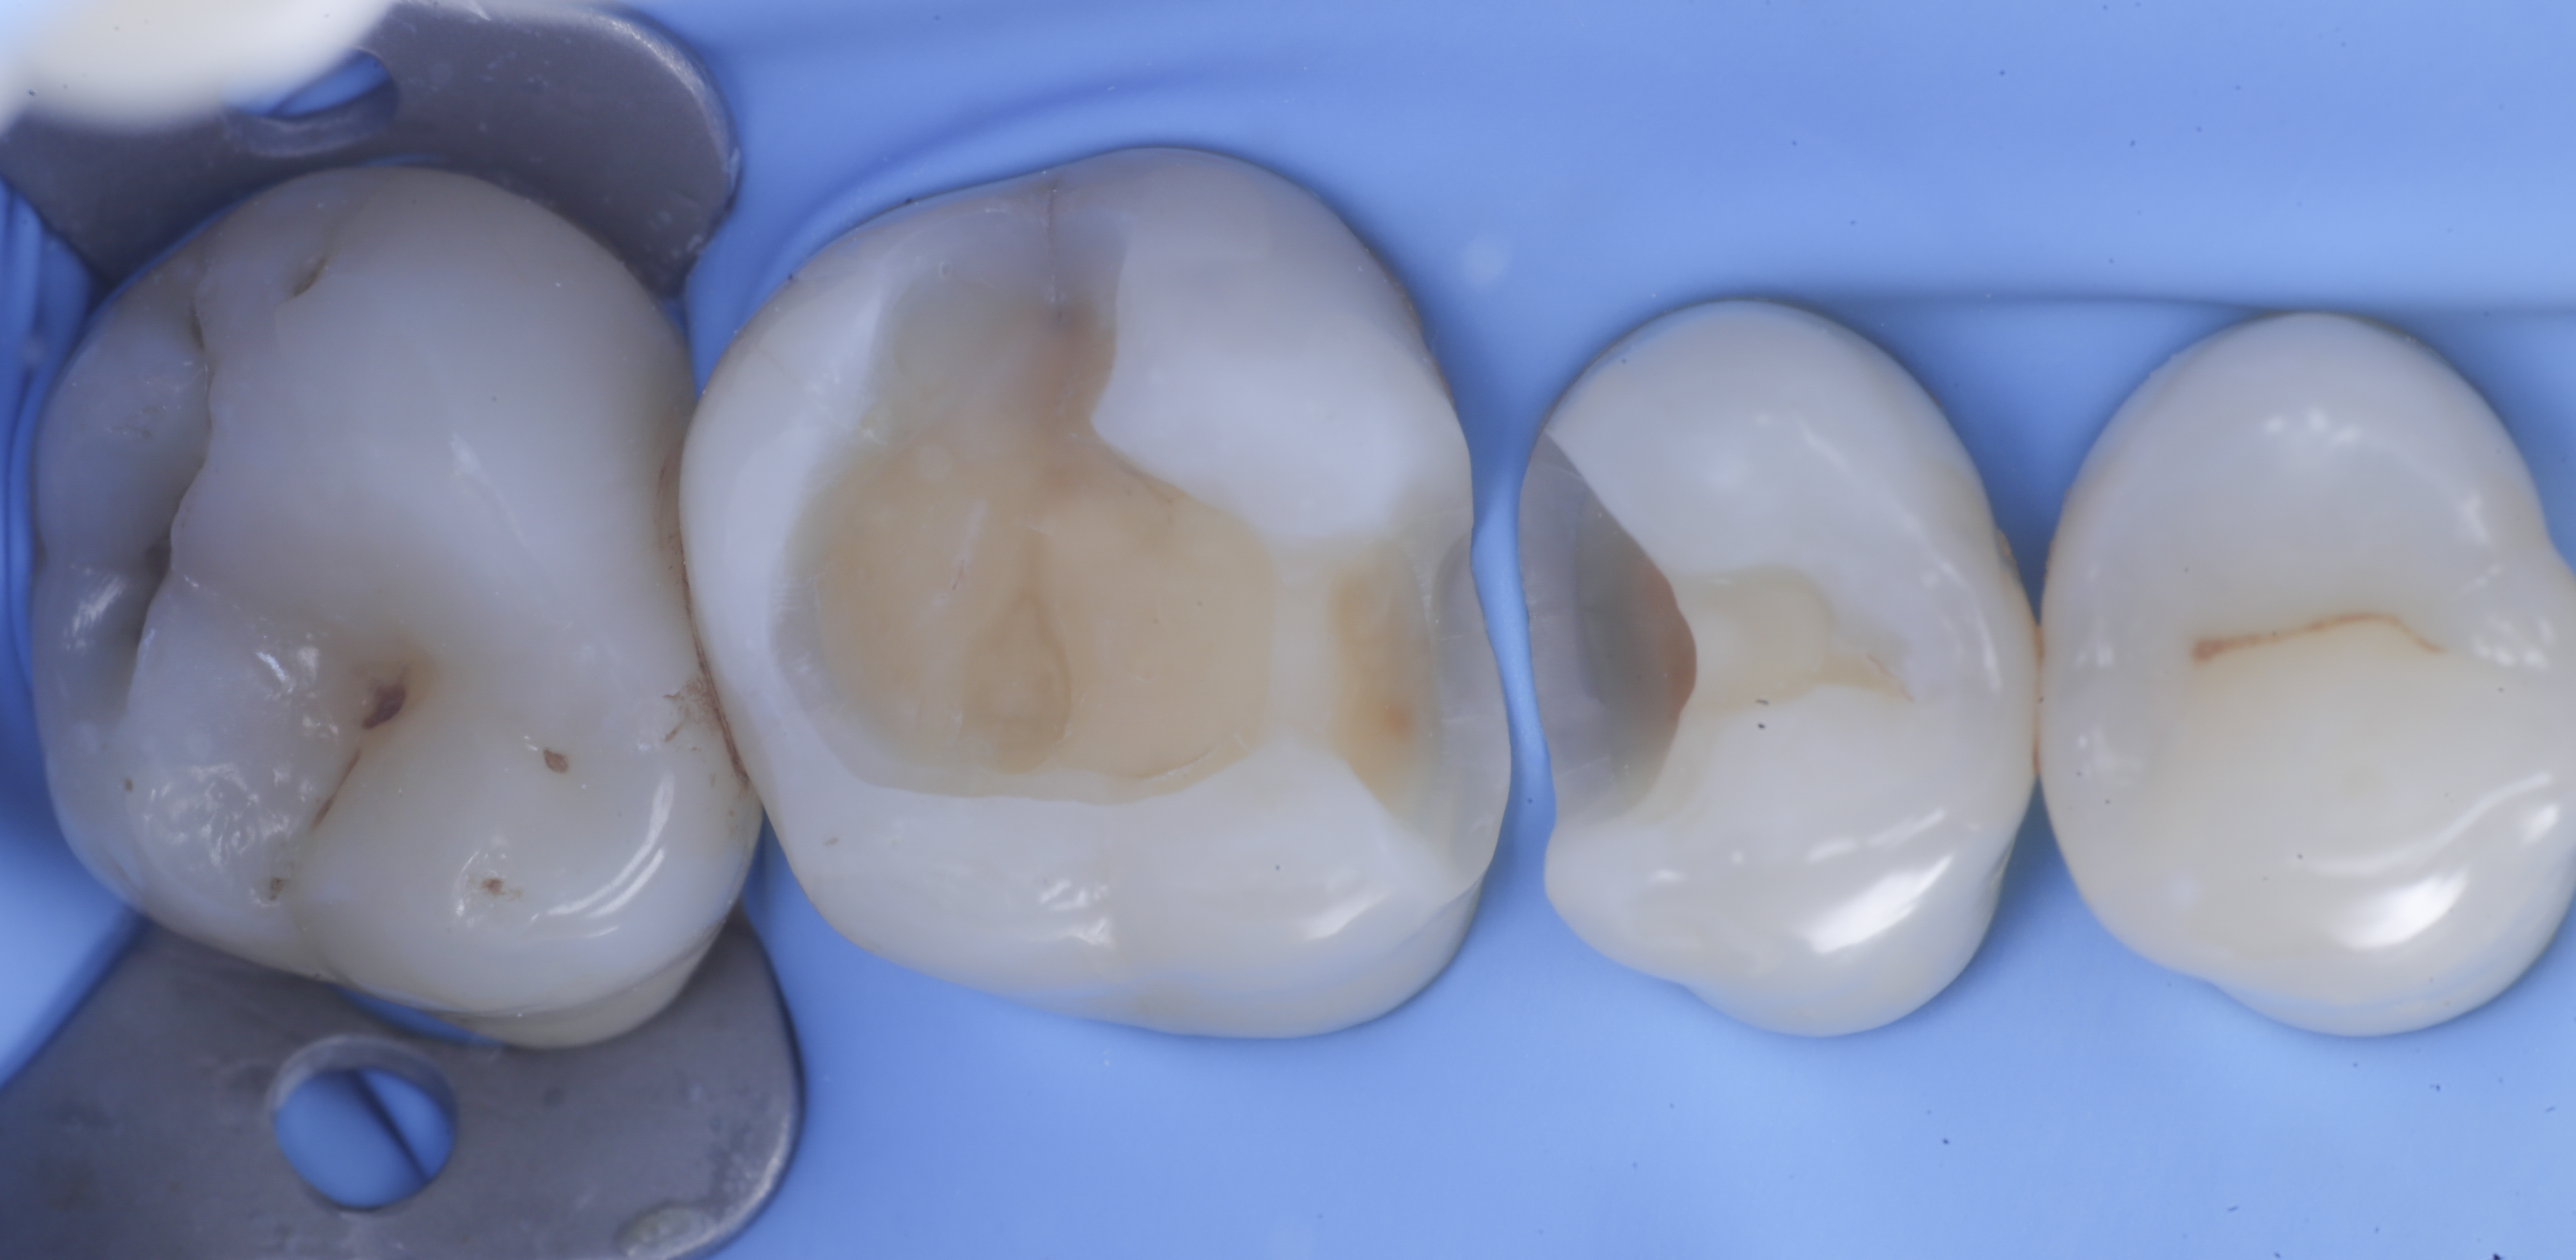

foto 2 Isolamento e aspetto delle cavità ultimate

foto 3 Aspetto vestibolare della cavità ultimate